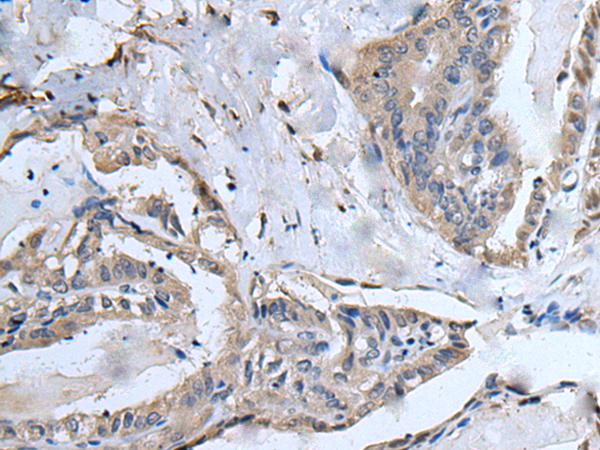

IHC positive control: |

Human esophagus cancer and human breast cancer |